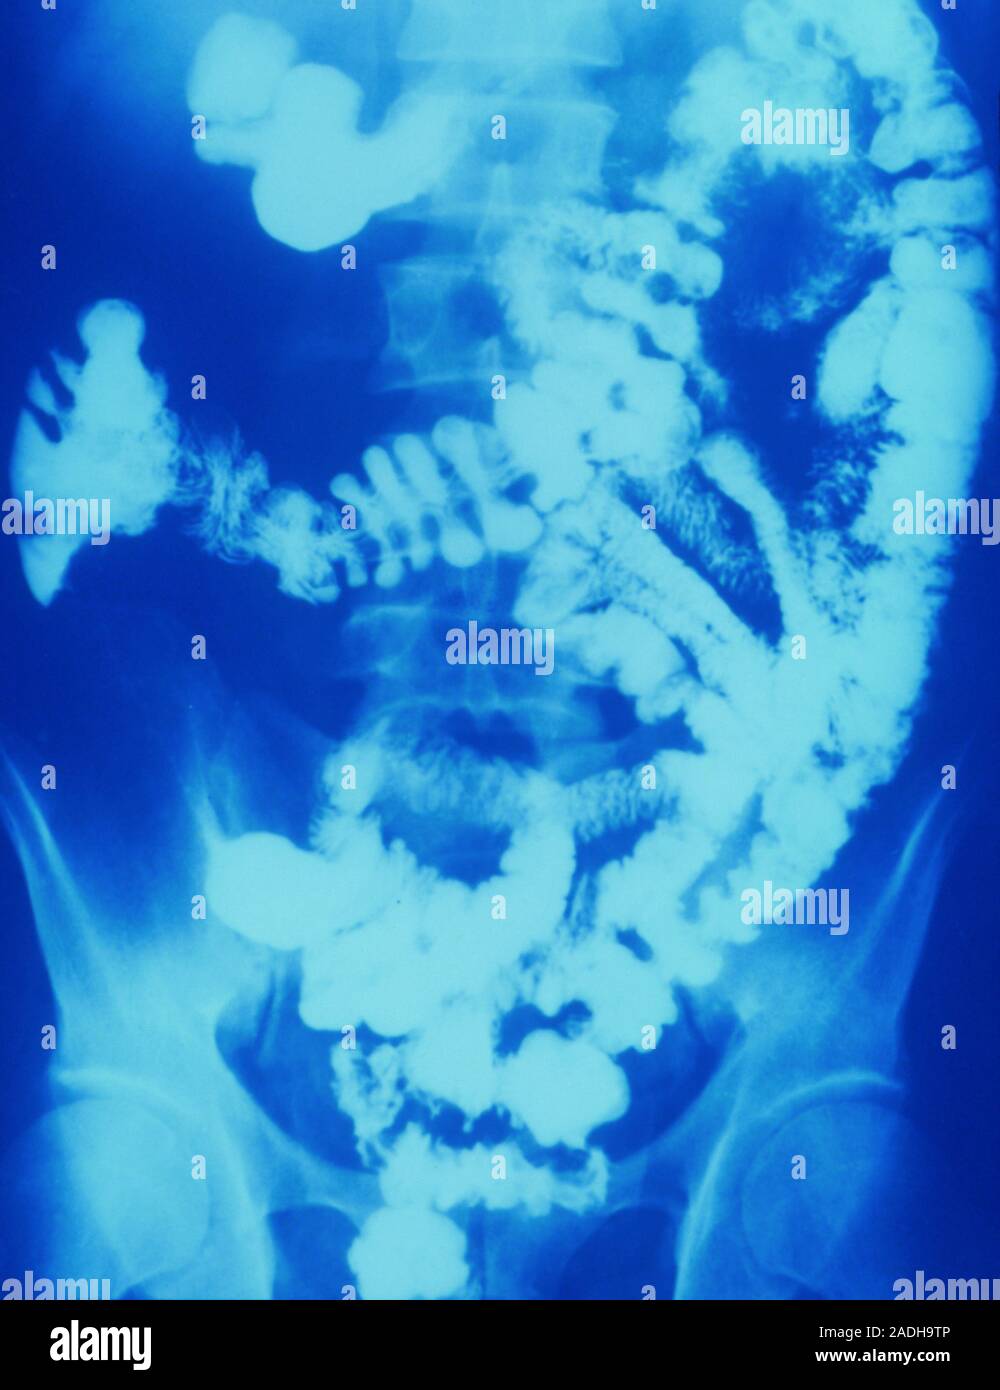

Abdominal barium Xray showing the intestine in Crohn's disease. Crohn Is Barium X Ray Dangerous The risks of a barium swallow test may include problems from radiation exposure, birth defects and intestinal issues. Modified barium swallow studies (mbsss) are a fluoroscopic exam that exposes patients to ionizing radiation. In each of the following tests,. As it passes through the body,. Why you might have it. Barium passes through the digestive system and does not cause. Is Barium X Ray Dangerous.